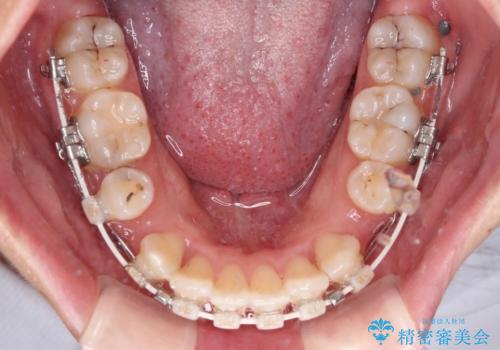

口元の突出感がない分、奥歯を前方に移動させる必要がありましたが、予定の2年間で無事に治療を終えることができました。

- 矯正装置

- 審美装置

- 2年1ヶ月